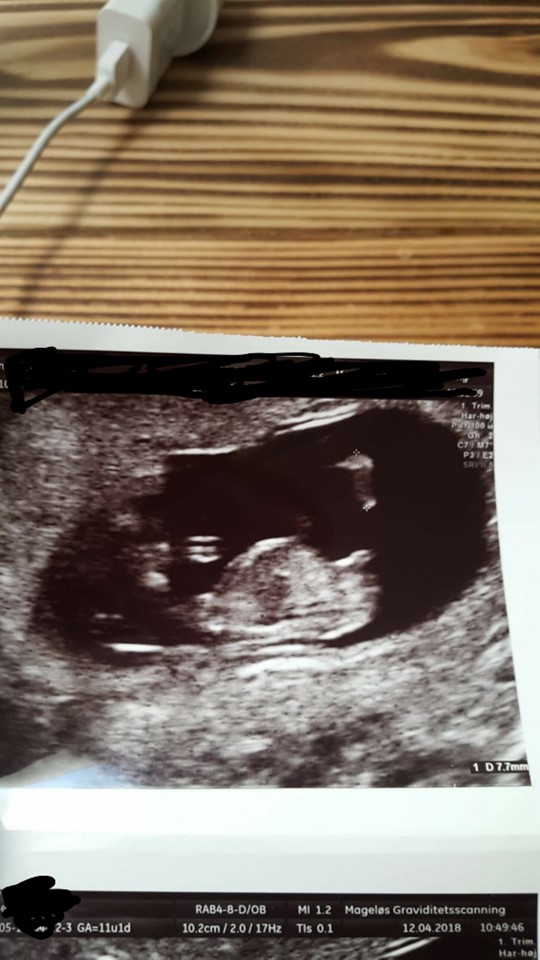

Har i dag været til scanning - er 11+1.

Kan man bruge Nub-teorien nu ? Kan ikke blive klog ved at google .. Det står forskelige ting - fra 11 til 13 uge ??

Et billede ;)

Vedhæftede fotos (klik for at se i fuld størrelse)